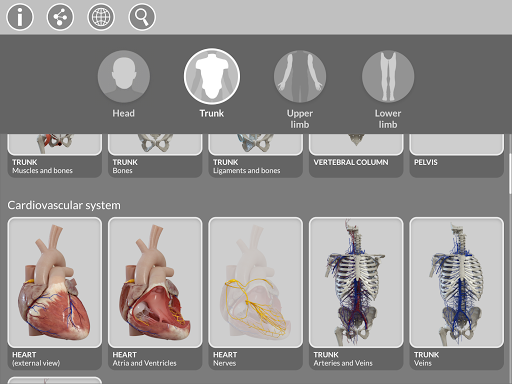

Pembagian berdasarkan wilayah dan tampilan yang telah ditetapkan sebelumnya memudahkan pengamatan dan studi bagian tunggal atau kelompok sistem dan hubungan antara organ yang berbeda.

"Anatomy - 3D Atlas" adalah aplikasi yang ditujukan untuk mahasiswa kedokteran, dokter, fisioterapis, paramedis, perawat, pelatih atletik, dan siapa pun yang tertarik untuk memperdalam pengetahuan mereka tentang anatomi manusia.

MODEL ANATOMI 3D

• Sistem muskuloskeletal

• Sistem kardiovaskular • Sistem

saraf • Sistem pernapasan • Sistem pencernaan • Sistem urogenital (pria dan wanita) • Sistem endokrin • Sistem limfatik • Sistem mata dan telinga FITUR • Antarmuka yang sederhana dan intuitif • Putar dan perbesar setiap model dalam ruang 3D • Opsi untuk menyembunyikan atau mengisolasi satu atau beberapa model yang dipilih • Filter untuk menyembunyikan atau menampilkan setiap sistem • Fungsi pencarian untuk menemukan setiap bagian anatomi dengan mudah • Fungsi penanda untuk menyimpan tampilan khusus • Rotasi cerdas yang menggerakkan pusat rotasi secara otomatis • Fungsi transparansi • Visualisasi otot melalui tingkat lapisan dari yang superfisial hingga yang terdalam • Dengan memilih model atau pin, istilah anatomi terkait akan muncul • Deskripsi otot: asal, • Tampilkan/ Sembunyikan antarmuka UI (sangat berguna dengan layar kecil) MULTIBAHASA • Istilah anatomi dan antarmuka pengguna tersedia dalam 11 bahasa: Latin, Inggris, Prancis, Jerman, Italia, Portugis, Turki, Rusia, Spanyol, Mandarin, Jepang, dan Korea • Istilah anatomi dapat ditampilkan dalam dua bahasa secara bersamaan PERSYARATAN SISTEM • Android 8.0 atau yang lebih baru, perangkat dengan RAM minimal 3GB Reversi

• Sistem kardiovaskular

• Sistem saraf

• Sistem pernapasan

• Sistem pencernaan

• Sistem urogenital (pria dan wanita)

• Sistem endokrin

• Sistem limfatik

• Sistem mata dan telinga